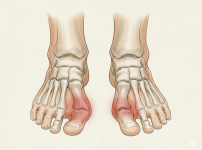

통풍성 관절염(Gouty Arthritis) | 서울건우 | 의학정보

정의통풍성 관절염은 단백질의 일종인 퓨린이 대사되면서 생성되는 요산 결정체가 관절 주변 조직에 쌓여 염증과 극심한 통증을 일으키는 질환입니다. 마치 비늘처럼 날카로운 요…